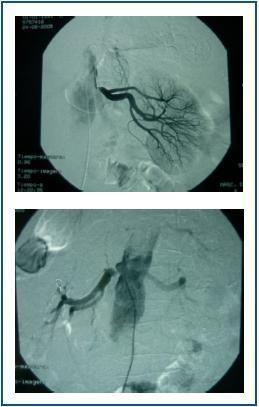

The arteriography detected stenosis in both renal arteries (figure 1), which was corrected with angioplasty and stent.

Figure 1.